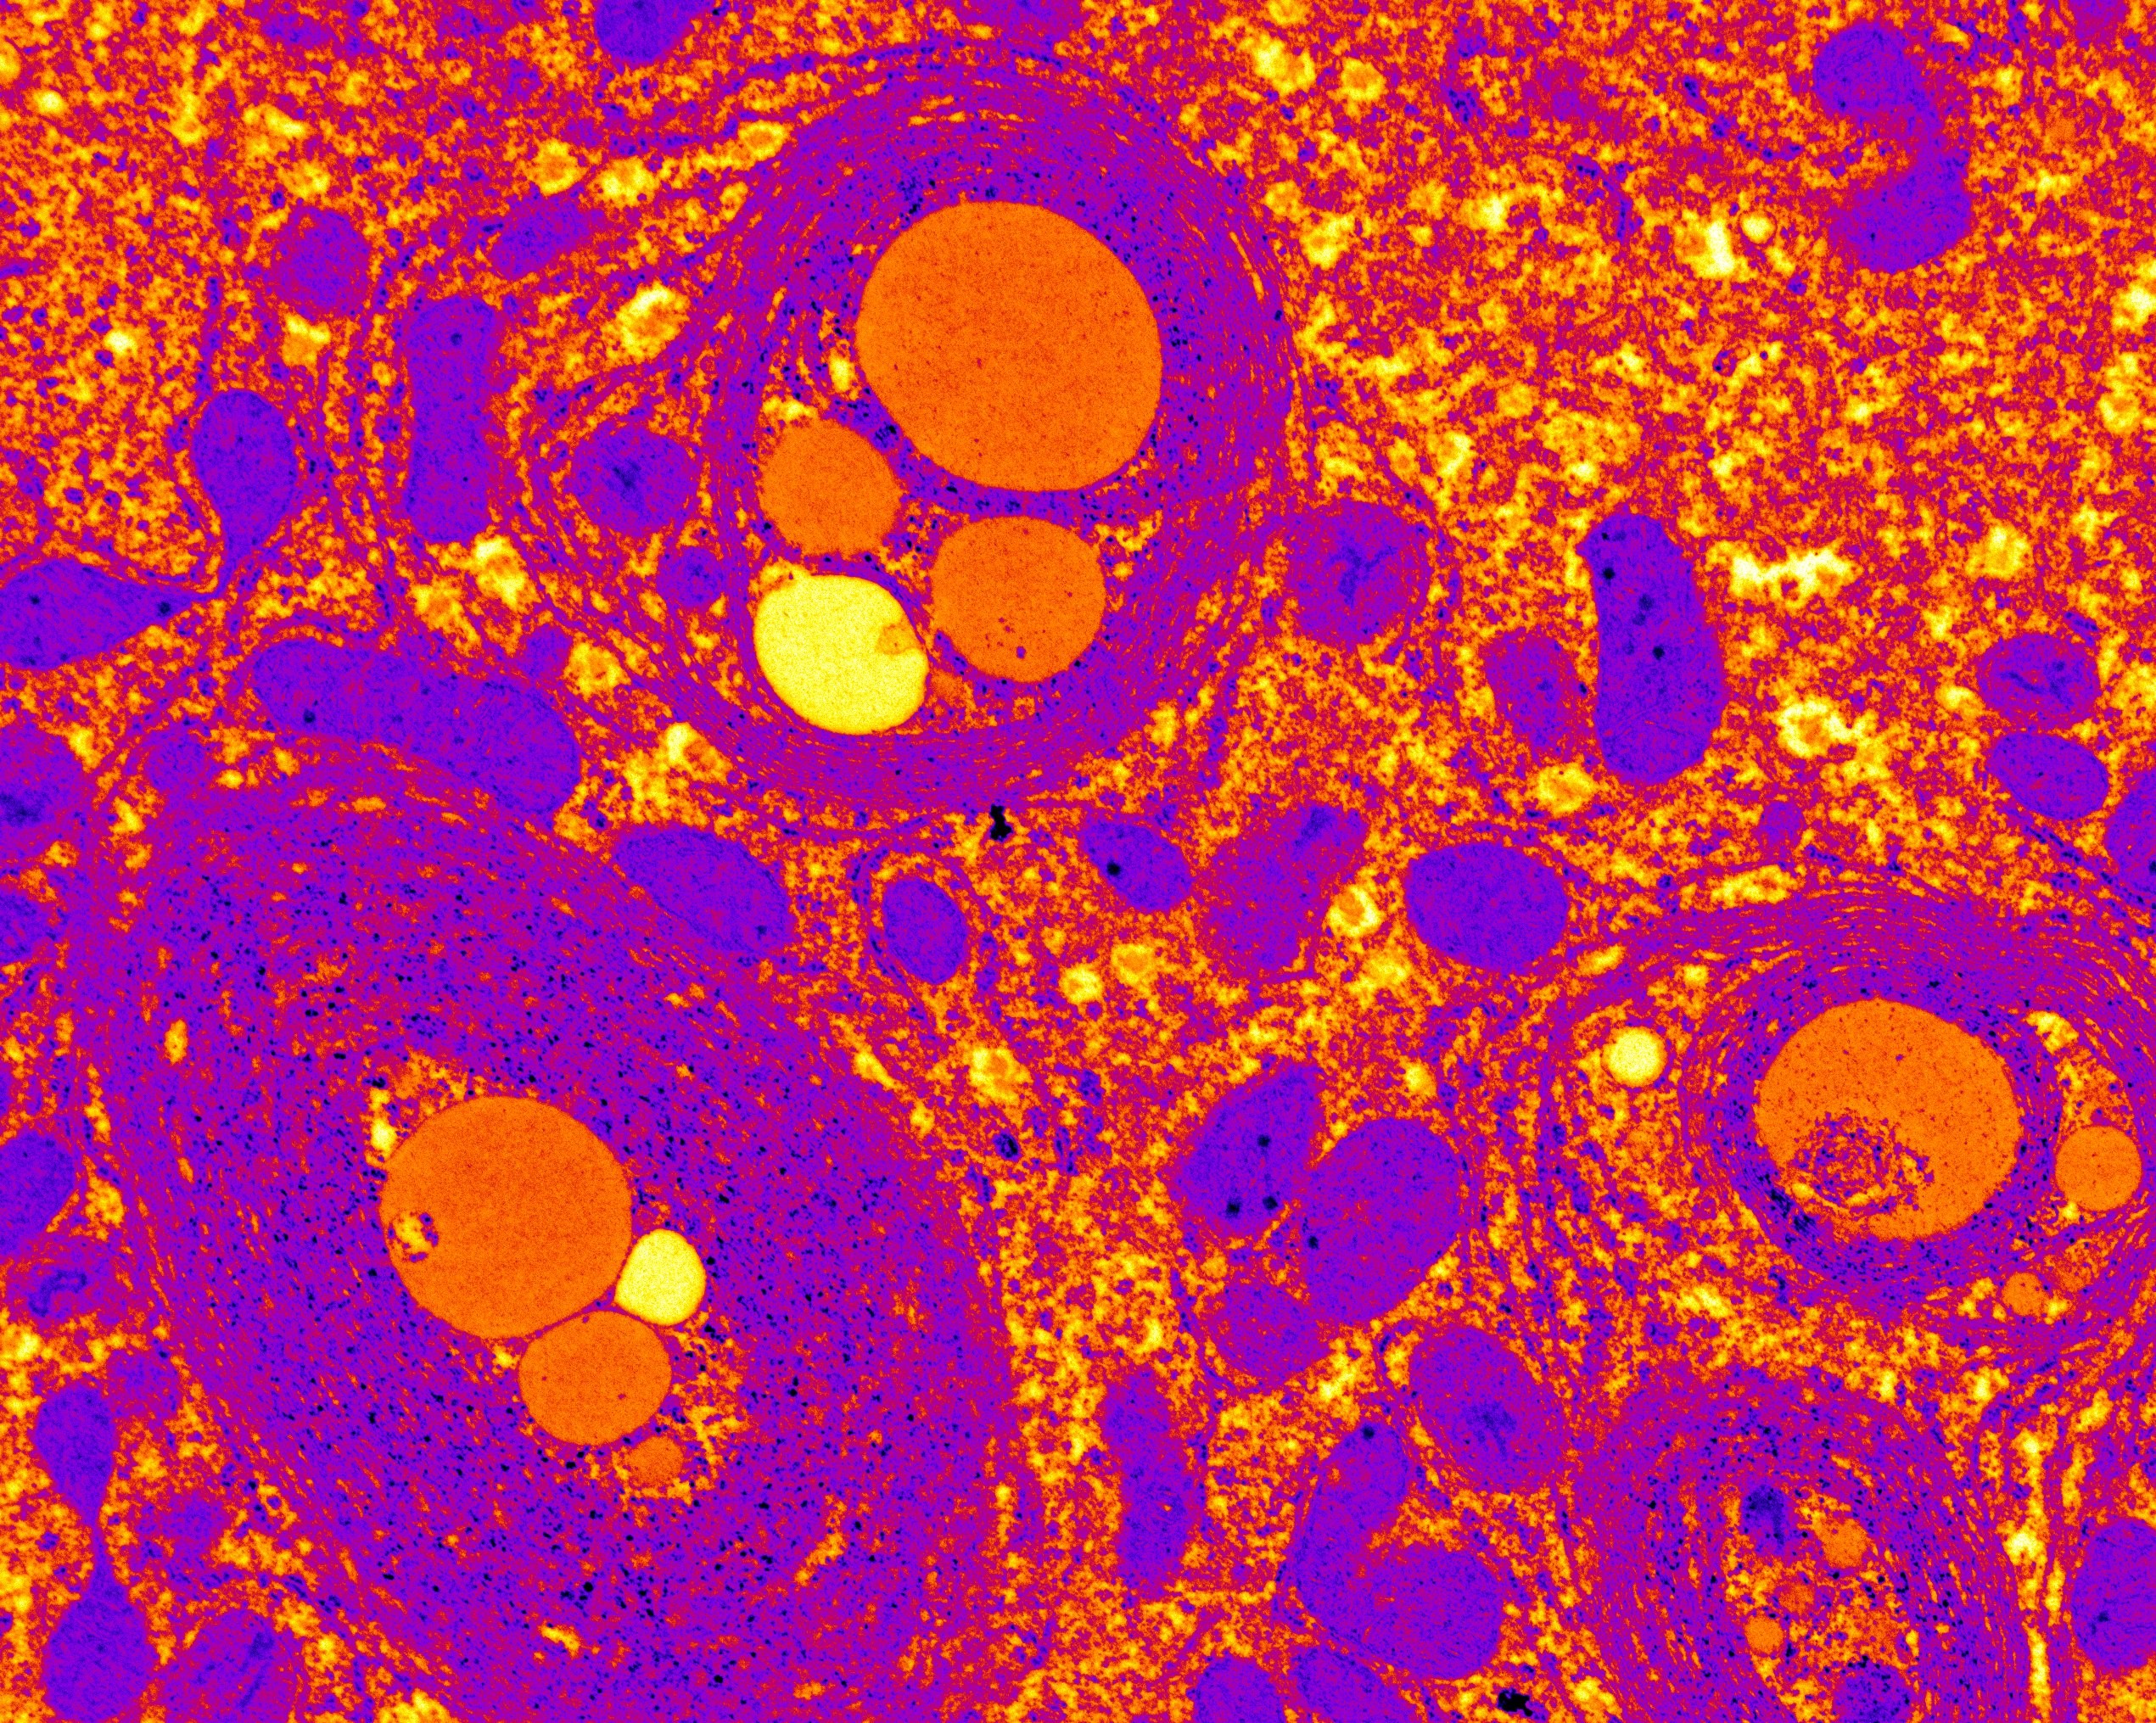

Autofagia deficiente de células hepáticas, tomadas con microscopio electrónico, que muestran la eliminación defectuosa de los desechos celulares

Este estudio, publicado recientemente en Nature Communications, demuestra que el proceso de reciclaje de componentes celulares que se encuentra activo en las células sanas y que es conocido como “autofagia” previene la acumulación de una proteína involucrada en el crecimiento del tumor. Los efectos que los científicos detectaron al bloquear la autofagia en los hígados de ratones resultaron muy similares a aquellos que se observan en pacientes humanos con la enfermedad de hígado graso no alcohólico (NASH), una patología crónica que incrementa el riesgo de desarrollar cáncer de hígado. Estos efectos se deben a la acumulación de la proteína Yes-associated (“Yap”), que, tal y como demuestra la investigación, promueve cambios en el comportamiento de las células del hígado incrementando el riesgo de padecer cáncer.